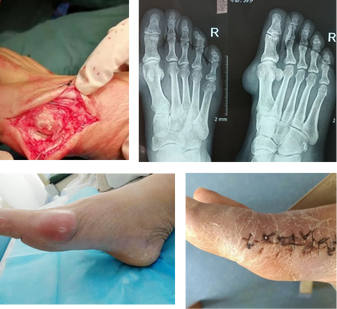

痛風石破潰且腐蝕關(guān)節(jié),治療后行走自如

患者:李應春

病情:全身多處巨大痛風石且破潰,已無法行走。

治療:經(jīng)過2次手術(shù)治療,取出全部痛風石,修復骨關(guān)節(jié),配合調(diào)理腎代謝,直至完全康復。